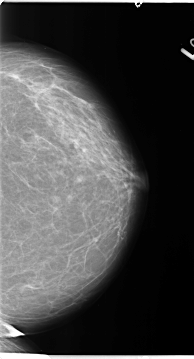

B_3121_1.LEFT_CC

LEFT_CC LINES 4664 PIXELS_PER_LINE 2520 BITS_PER_PIXEL 12 RESOLUTION 50 NON_OVERLAY